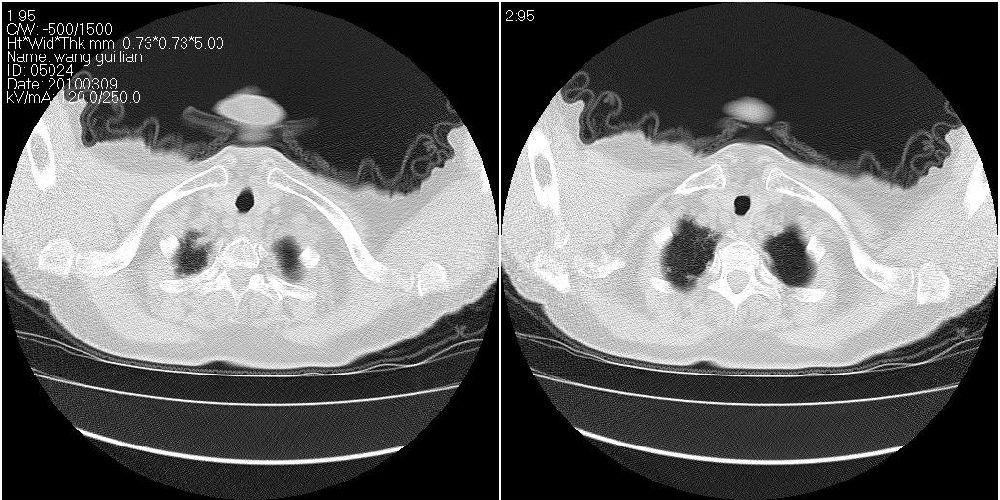

女性,72岁。去年9月份发现肺部病变,诊为肺结核并进行正规治疗至今,但复查后发现ct表现几乎没有变化。

右侧中叶支气管明显狭窄,建议行纤支镜检查!

右中间段支气管局限性狭窄,右中叶支气管亦稍显狭窄,但并未见明显占位表现,半年多了,无变化也许是好事,可能为炎性狭窄,建议继续随访。

双肺继发型tb并右中叶内膜tb,轻度支扩,左下胸膜肥厚粘连。

右中叶炎性改变,支气管狭窄但较光滑,占位可能性不大。

右中间段支气管局限性狭窄,右中叶支气管亦稍显狭窄.

双肺继发性肺结核并右肺中叶节段性肺不张,左下胸膜肥厚粘连。

右肺中叶节段性肺不张,考虑结核或慢性炎症,建议做纤支镜检查。

双肺继发性肺结核并右肺中叶节段性肺不张